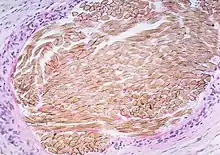

| Picture of a granuloma (without necrosis) as seen through a microscope on a glass slide: The tissue on the slide is stained with two standard dyes (hematoxylin: blue, eosin: pink) to make it visible. The granuloma in this picture was found in a lymph node of a patient with a Mycobacterium avium infection. | |

Macrophages (specifically histiocytes) are the cells that define a granuloma. They often fuse to form multinucleated giant cells (Langhans giant cell).[7] The macrophages in granulomas are often referred to as "epithelioid". This term refers to the vague resemblance of these macrophages to epithelial cells. Epithelioid macrophages differ from ordinary macrophages in that they have elongated nuclei that often resemble the sole of a slipper or shoe. They also have larger nuclei than ordinary macrophages, and their cytoplasm is typically pinker when stained with eosin. These changes are thought to be a consequence of "activation" of the macrophage by the offending antigen.

The other key term in the above definition is the word "organized" which refers to a tight, ball-like formation. The macrophages in these formations are typically so tightly clustered that the borders of individual cells are difficult to appreciate. Loosely dispersed macrophages are not considered to be granulomas.